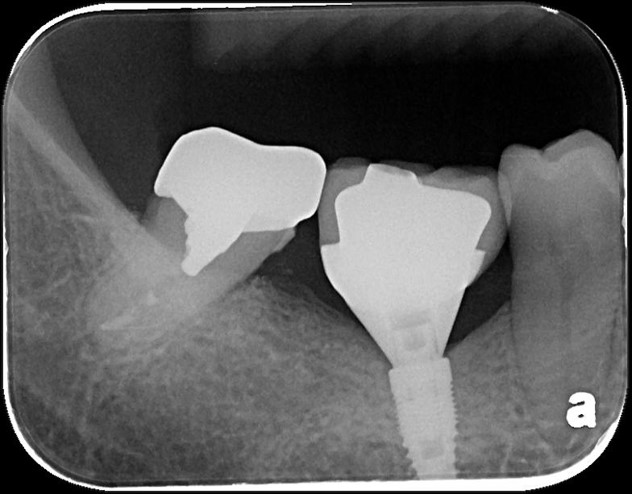

治療前,蛀牙已侵犯至牙髓

顯微根管治療

鑄造金屬釘柱